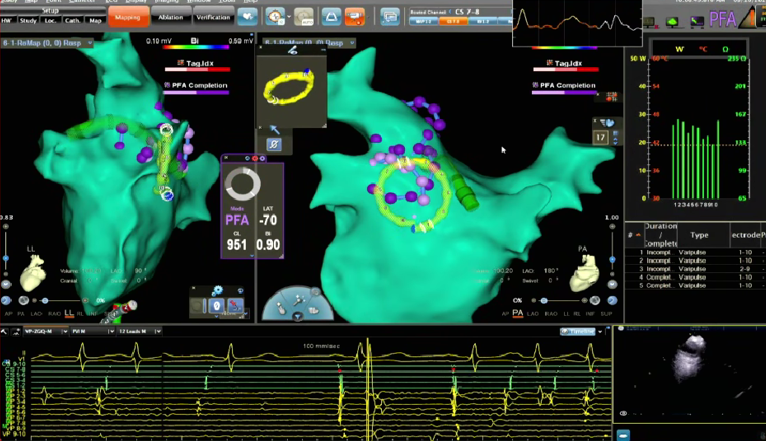

VARIPULSE作为首款搭载Carto三维平台的脉冲消融产品,自上市以来,凭借其“高效”、“绿色”与“贴靠”三大核心价值,赢得了国内专家的广泛认可。上市百日内,已成功服务近七百位中国患者,实现近100%的即刻手术成功率,平均消融时间仅35分钟,且超过20%的手术在零射线条件下完成。凭借这一卓越的临床表现,VARIPULSE不仅为医疗工作者提供了更先进、更全面的治疗方案,也为广大患者带来了恢复窦性心律的新希望。

在本次电生理手术直播周期间,20位资深术者通过实时手术演示,全方位展现了 VARIPULSE脉冲消融系统在房颤治疗中的高效与绿色优势,将其临床性能推向极致。手术数据亮眼——全场直播的平均消融时间仅28分钟,充分印证了该系统的高效性;学术交流同样热烈,超50位领域专家齐聚线上,围绕‘麻醉方案优化’‘、“术式创新选择”、”并发症预防策略”等脉冲电场消融领域的核心热点话题,展开深度研讨与观点碰撞。